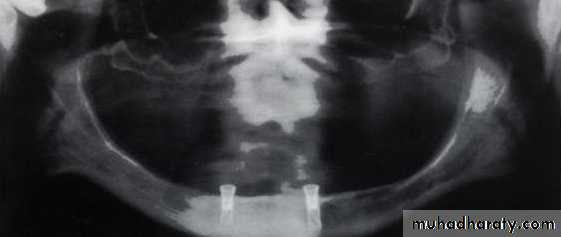

Implant supported over denture

Implant Over-DentureAn implant over-denture connects to cylinder-like configurations (called implants) that have been surgically implanted into jaw bone.

The denture appears like a traditional prosthesis. However, that part of the denture overlying implants is modified to retain various semi-rigid attachments that receive implant extensions projecting above the gum. This arrangement helps keep a denture securely in place while eating, speaking and during other oral activities, but still allows easy self-removal of the denture for cleaning purposes.